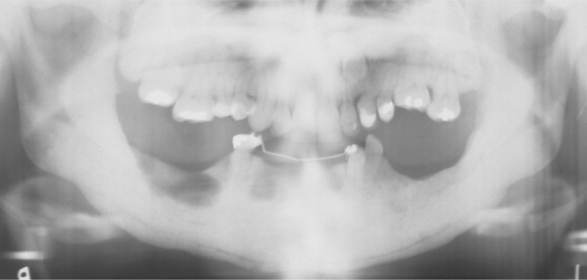

Cleidocranial Dysplasia

Oral complications of cleidocranial dysplasia

High arched palate

INCREASED prevalence of cleft palate

Prolonged retention of deciduous teeth

Delayed or failure of eruption of permanent teeth

Abnormally shaped teeth

Numerous unerupted permanent and supernumerary teeth